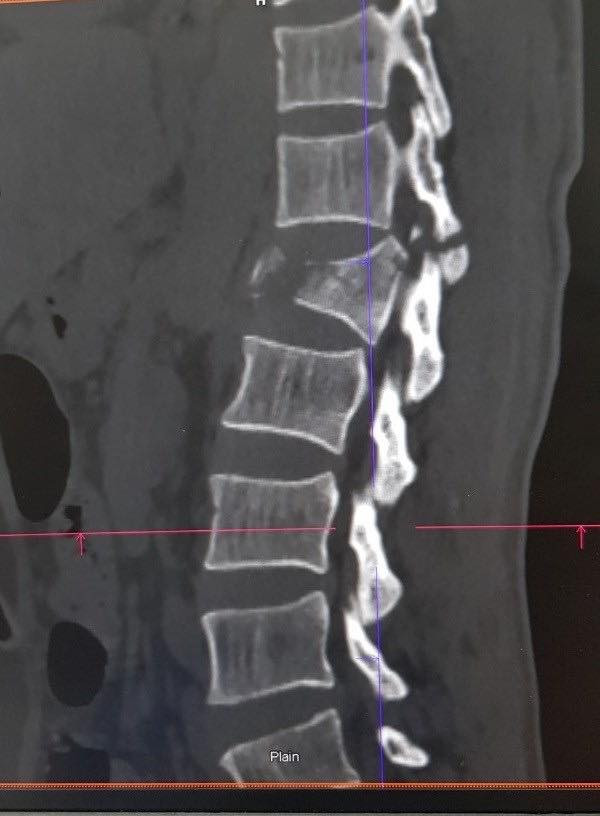

Vụ tai nạn khiến thân đốt sống L1 của anh G. bị vỡ thành nhiều mảnh, toàn thân đau đớn. Để chữa trị cho nam bệnh nhân, các bác sĩ quyết định mổ nắn chỉnh, cố định lại cột sống.

| Ảnh minh họa đoạn đốt sống L1 trên cơ thể |